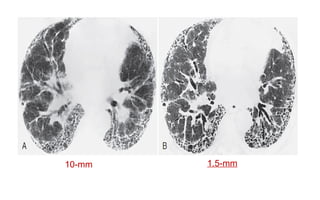

CT spatial resolution (high contrast resolution)

For two objects to be seen as separate the detectors must be able to

identify a gap between them.

10-mm 1.5-mm

A standard kernel A bone kernel

Utilizing a bone, sharp, high frequency or high pass algorithm during reconstruction

can improve the spatial resolution.

The ability ofthe image to differentiate between structures with very different attenuation characteristics (CT numbers ) when they are very close together.  A high level of spatial resolution can be achieved by having small pixels and thin slices.  Smaller focal spot produce high spatial resolution (increase the sharpness).  decreasing the pitch increase resolution. CT spatial resolution (high contrast resolution) For two objects to be seen as separate the detectors must be able to identify a gap between them.

A standard kernelA bone kernel

Utilizing a bone,sharp, high frequency or high pass algorithm during reconstruction can improve the spatial resolution.